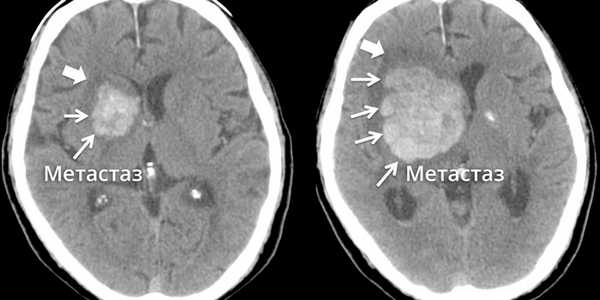

Метастазы в головном мозге.

Метастаз в головном мозге в динамике